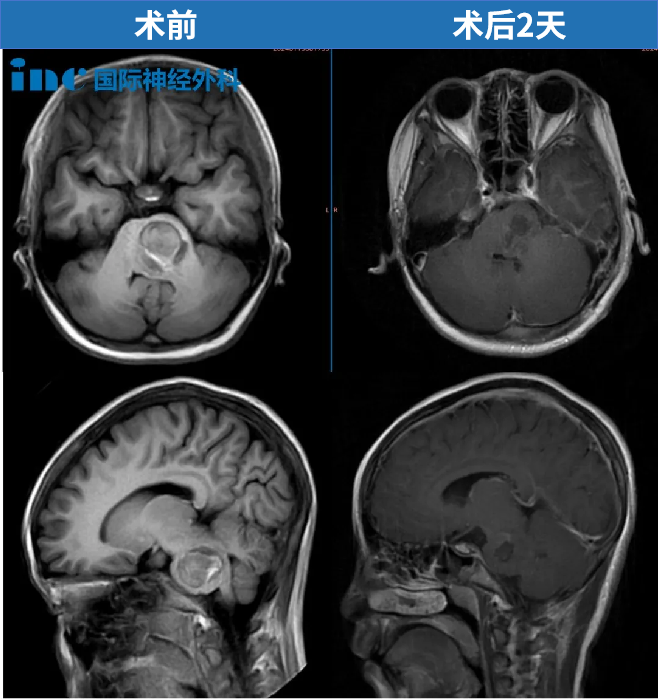

术后第2天,孩子便转出了ICU。原本预计需要在ICU观察两天,因此我们对此感到非常惊讶,恢复速度如此之快。提前一天转出ICU,让我们更加欣喜。

术后第2天查房,贝贝肢体活动正常。“今天早上喝了很多粥”看着孙女恢复得越来越好,贝贝奶奶满怀感激,她对贝贝说道“这是救你命的爷爷”。我们从ICU转入普通病房,第一眼看到孩子时,内心充满了无比的喜悦。住院时间并不长,我们便顺利出院了。恢复情况确实远超预期,因为我查阅的许多资料都提到或多或少会遗留后遗症,但我们的结果绝对超出了最初的设想。

巴教授为她进行了术后随访,评估结果为“影像学片子非常好,脑干形态已恢复正常,1年后再次复查即可”。如同凤凰涅槃重生,经历了与死神的擦肩而过,贝贝必将勇往直前!当初情况紧急,巴教授制定的治疗方案核心在于尽快实施手术。实践结果证实,他的治疗方案是完全正确的。看到孩子如今各方面恢复得特别理想,我们由衷感谢巴教授。